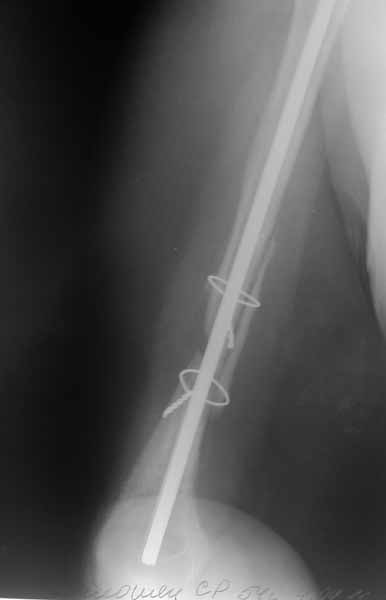

После БИОС

[ Ответить ]